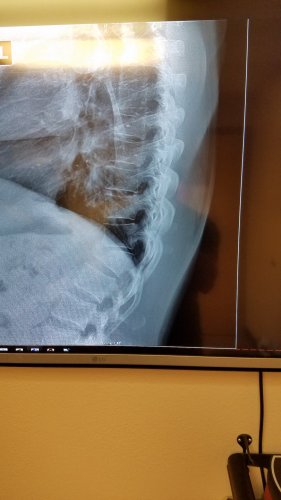

@Cordawayconstruction said..."Last time I sled down a hill in a toboggan I broke my back. Sledding is the devil"...good grief...that was not a good trip. I've never injured myself tobogganing....or skating or skiing either....thank goodness.

It was the dumbest thing that's ever happened to me In my life. Went off a little jump. I even slowed way down cause I was t trying to be crazy or get hurt. Landed on my but sitting upright in it and my t-12 burst. It happened Dec 27 2015, this pic was an x-ray taken 4 months ago. Stick to snowboarding, it's less dangerous. Lol